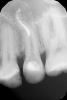

Marina_A Опубликовано 6 июня, 2013 Поделиться Опубликовано 6 июня, 2013 Пациентка пришла с целью санации).Я посмотрела на снимок очередного зуба и ахнула Но все оказалось не так плохо, нам удалось пройти каналы. ну и конечно же, как без паффа? зато какой четкий знак вопроса! 8 Ссылка на комментарий

Kivilgar Опубликовано 6 июня, 2013 Поделиться Опубликовано 6 июня, 2013 Пациентка пришла с целью санации).Я посмотрела на снимок очередного зуба и ахнула 1.PNG Но все оказалось не так плохо, нам удалось пройти каналы.2.PNG ну и конечно же, как без паффа? зато какой четкий знак вопроса! 3.PNGЗдорово получилось. Какими файлами? Ссылка на комментарий

Marina_A Опубликовано 6 июня, 2013 Автор Поделиться Опубликовано 6 июня, 2013 Здорово получилось. Какими файлами?ручными, а затем профайлами и протейперами) Ссылка на комментарий